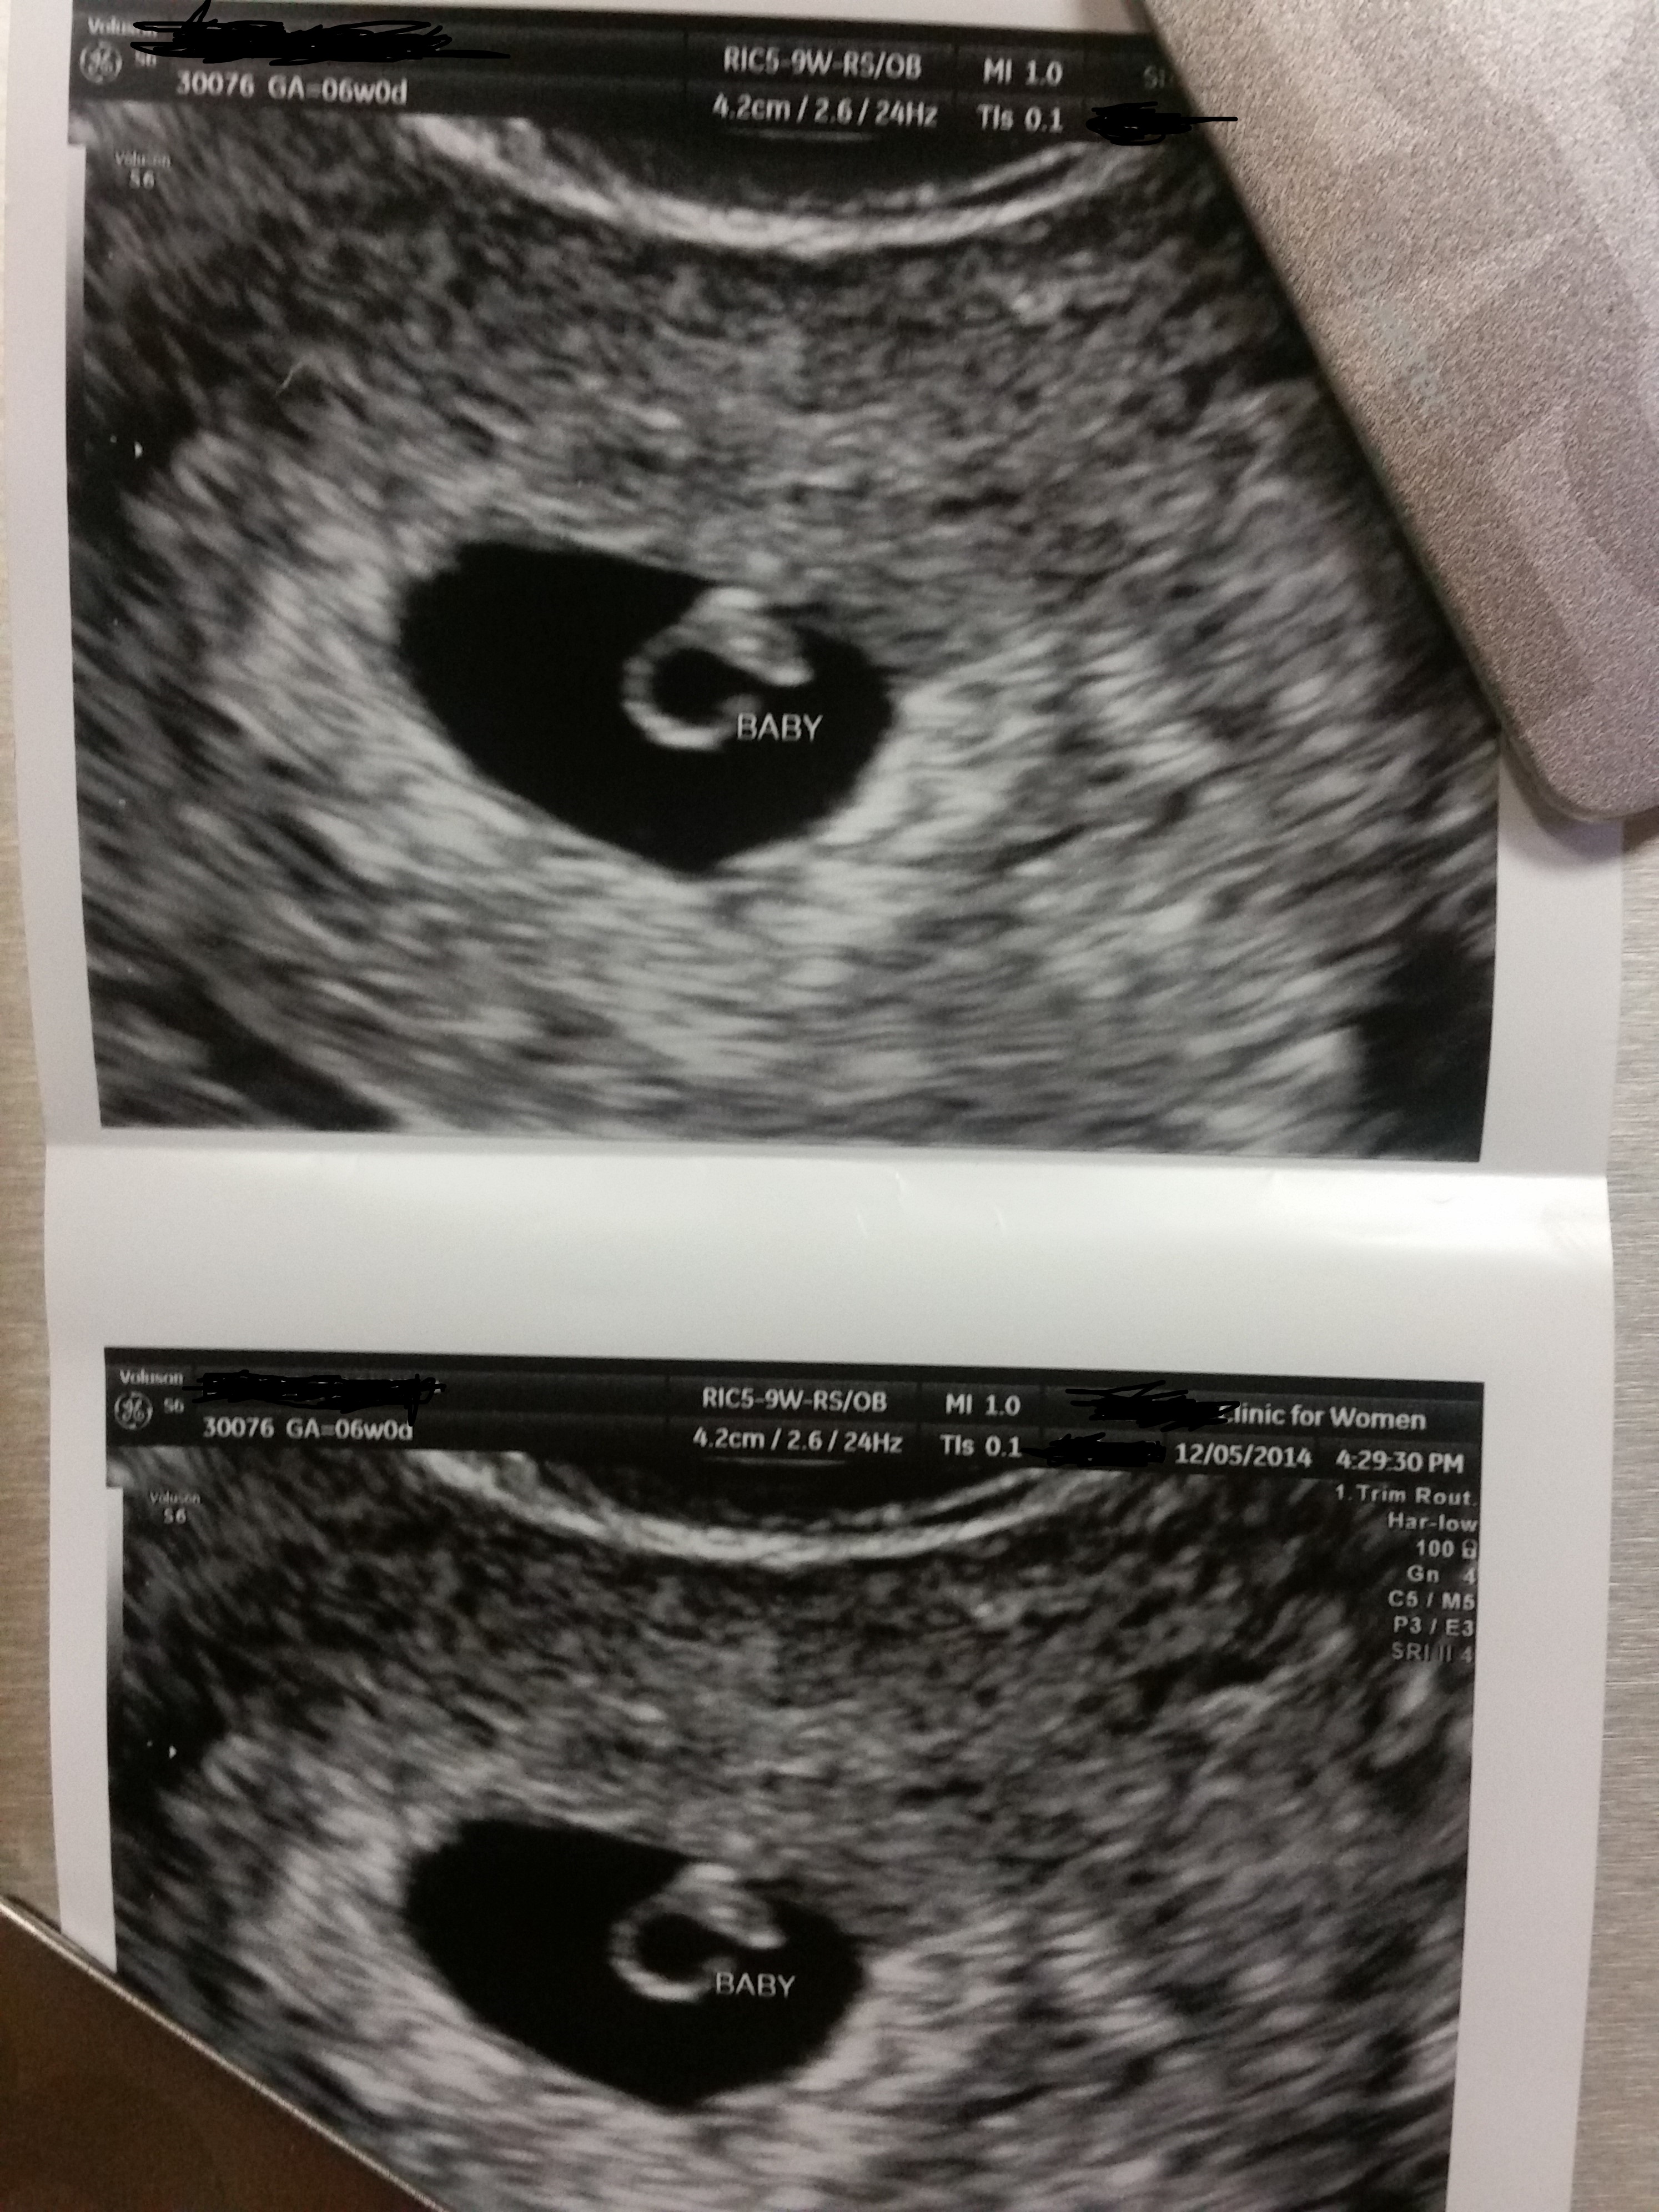

Ramzi Guesses?? Exactly 6 wks T/V US

The heart rate was 118. I asked the ultrasound tech where the baby had implanted she said that it was right at the top in the middle which kinda worries me cause I had a partial septate resceted in Dec 2011 and if it implanted on top of the rection site it is a higher chance of placental abruption.

This was transvaginal of course :)

Attachment 22517